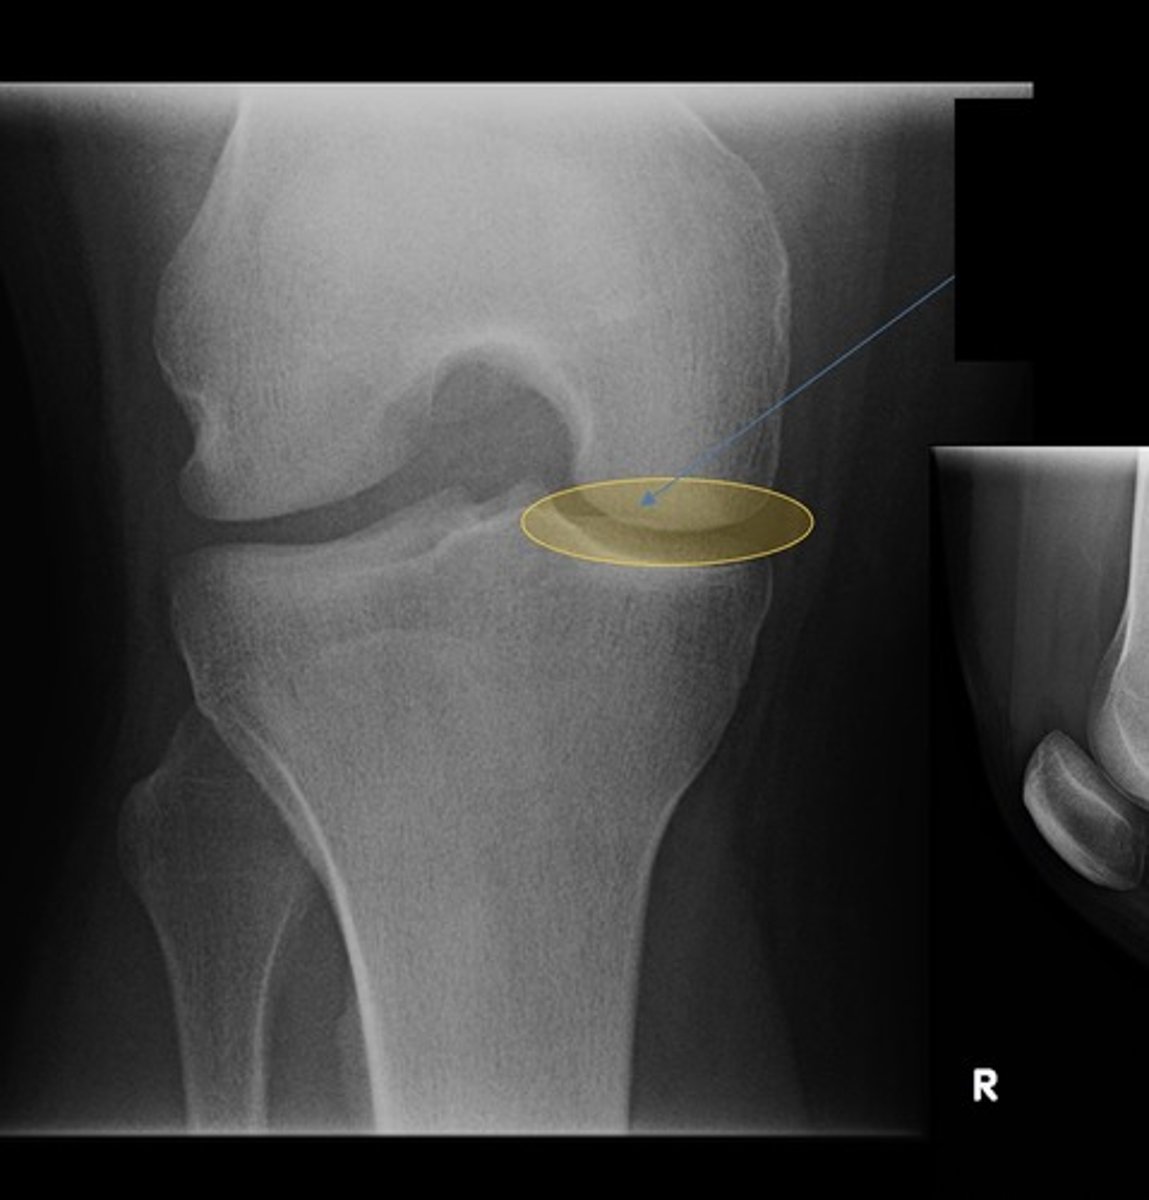

R and L plateaus

lateral tibiofemoral joint

medial tibiofemoral joint

intercondylar notch